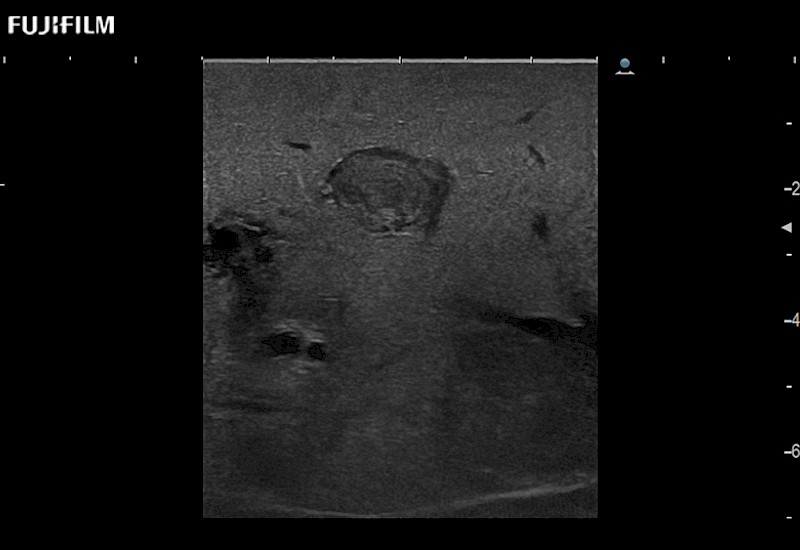

Extraordinary high-resolution digital imaging

- Instant feedback on tumor margin delineation

- Valuable information to guide tumor resections

- Instant feedback on tumor margin delineation

- Exceptional near and far-field resolution

- Instant feedback on tumor margin delineation

- Instant feedback on tumor margin delineation

- Instant feedback on tumor margin delineation

- Instant feedback on tumor margin delineation

- Valuable information to guide tumor resections

- Instant feedback on tumor margin delineation

- Valuable information to guide tumor resections

- Instant feedback on tumor margin delineation

- Valuable information to guide tumor resections

- Instant feedback on tumor margin delineation

- Valuable information to guide tumor resections

- Instant feedback on tumor margin delineation